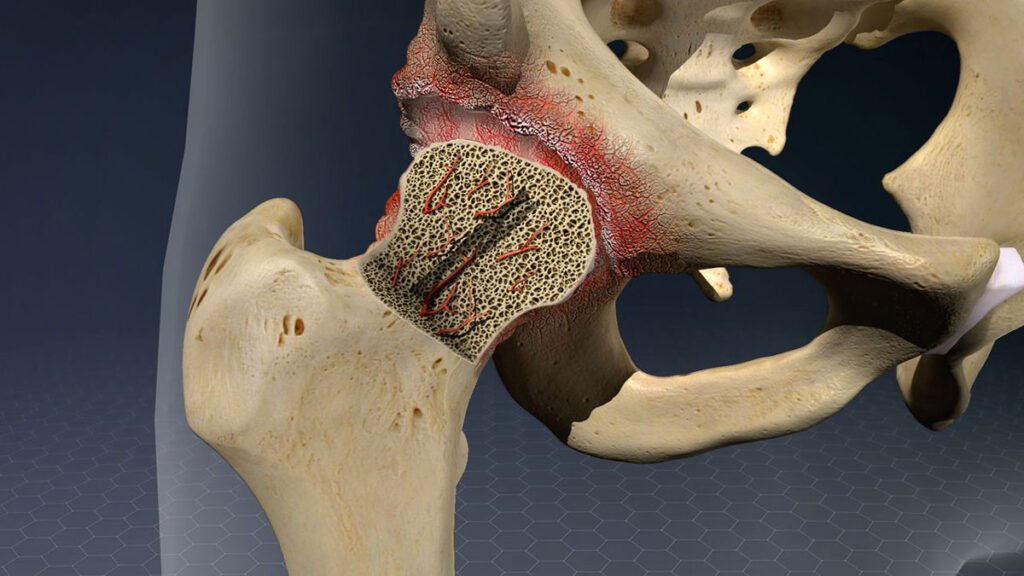

Avascular Necrosis of the Hip

A loss of blood supply to the hip bone leading to joint collapse and chronic pain

Avascular necrosis (AVN) of the hip, also referred to as osteonecrosis, is a condition where the blood flow to the femoral head (the ball portion of your hip joint) becomes reduced or completely interrupted. Without adequate circulation, the bone tissue begins to die, leading to weakening and eventual collapse of the joint surface. Over time, this can result in severe pain, stiffness, and the development of hip arthritis.

Avascular necrosis (AVN) of the hip develops when the blood supply to the femoral head becomes disrupted or significantly reduced. Without adequate blood flow, the bone cells in the hip begin to die, which can weaken the bone structure, lead to joint collapse, and eventually cause arthritis.

Stage 3: femoral head collapse

- Description: The femoral head begins to flatten or collapse, indicating significant bone death.

- Imaging findings: Crescent sign on X-ray, indicating a fracture under the surface of the bone.